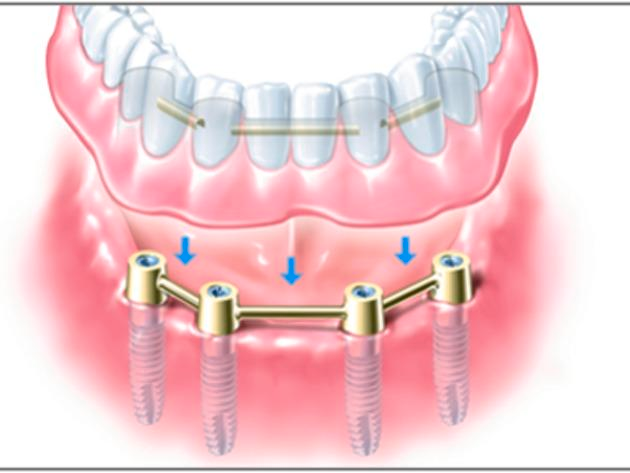

Zahnloser Kiefer

Wenn Ihnen im Unterkiefer fast alle oder sogar alle Zähne fehlen, haben Sie mit Implantaten trotzdem gut lachen. Denn schon zwei bis vier Implantate reichen aus, um einer Vollprothese festen Halt zu geben. Die Befestigung erfolgt mit speziellen Haltesystemen, die aus zwei Elementen bestehen. Eines wird dauerhaft auf die Implantate gesetzt, das Gegenstück in die Prothese eingearbeitet.

Beim Einsetzen verbinden sich die beiden Elemente, ähnlich wie bei einem Druckknopf: Ihre Prothese sitzt fest. Zum Reinigen können Sie sie jederzeit leicht wieder abnehmen.

Auf mindestens sechs Implantaten kann auch eine Brücke dauerhaft an Ihrem Kiefer verankert werden. Der Zahnersatz sitzt dann so fest, dass auf den stützenden rosa Prothesenkunststoff verzichtet werden kann. Im Oberkiefer bleibt in jedem Falle der Gaumen frei von Prothesenmaterial.